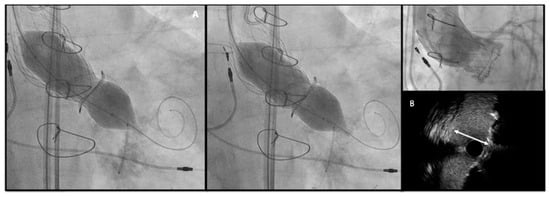

Bioprosthetic heart valves (BHV) have been increasingly implanted instead of mechanical valves in patients undergoing surgical aortic valve replacement (SAVR). Structural valve deterioration (SVD) is a common issue at follow-up and can justify the need for a reintervention. In the evolving landscape of interventional cardiology, valve-in-valve transcatheter aortic valve replacement (ViV TAVR) has emerged as a remarkable innovation to address the complex challenges of patients previously treated with SAVR and has rapidly gained prominence as a feasible technique especially in patients at high surgical risk. On the other hand, the expanding indications for TAVR in progressively younger patients with severe aortic stenosis pose the crucial question on the long-term durability of transcatheter heart valves (THVs), as patients might outlive the bioprosthetic valve.